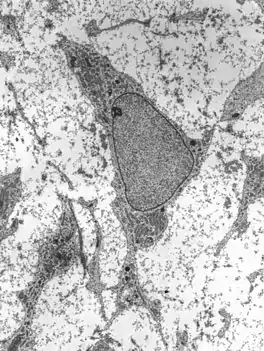

![]() Transmission electron micrograph of an adult stem cell displaying typical ultrastructural characteristics. | |